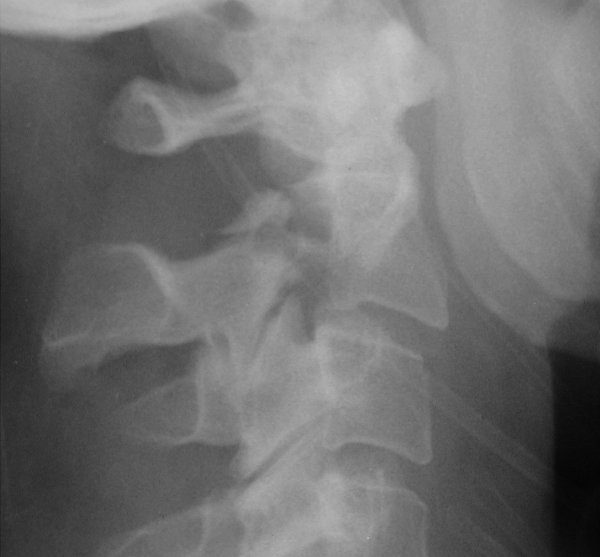

Return to Hangman's Fracture